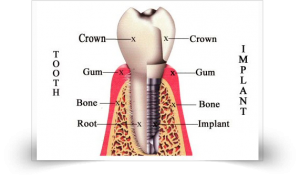

Dental Implants are surrogate tooth roots. Dental implants provide a tough foundation for permanent or removable prosthesis (replacement teeth) that are created to match your natural teeth. It is manufactured from the biologically neutral pure titanium which is accepted by the human body. These dental implants blend with the jawbone to create a protected foundation for the tooth substitution. ISO 9001:2015 Certified Smile Please Super Speciality Dental Clinic & our Specialist Dr. Sharad Kumar M.D.S.(ORTHO) provides the most modern technology and facilities for replacement of missing teeth with Dental implants in Vashi, Navi Mumbai, India.

The single tooth implant restoration include three parts, Implant that restore the tooth root, the abutment that support the crown and the prosthetic crown itself. The crown is may cemented onto abutment or held in place with a screw. With today's development, there are an assortment of implant systems, models and ranges available. Every line is outfitting the individual's requisites of patents. A single tooth implant with crown is one of the best everlasting restorations. This solution looks and functions akin to a natural tooth.

The single tooth implant restoration include three parts, Implant that restore the tooth root, the abutment that support the crown and the prosthetic crown itself. The crown is may cemented onto abutment or held in place with a screw. With today's development, there are an assortment of implant systems, models and ranges available. Every line is outfitting the individual's requisites of patents. A single tooth implant with crown is one of the best everlasting restorations. This solution looks and functions akin to a natural tooth.